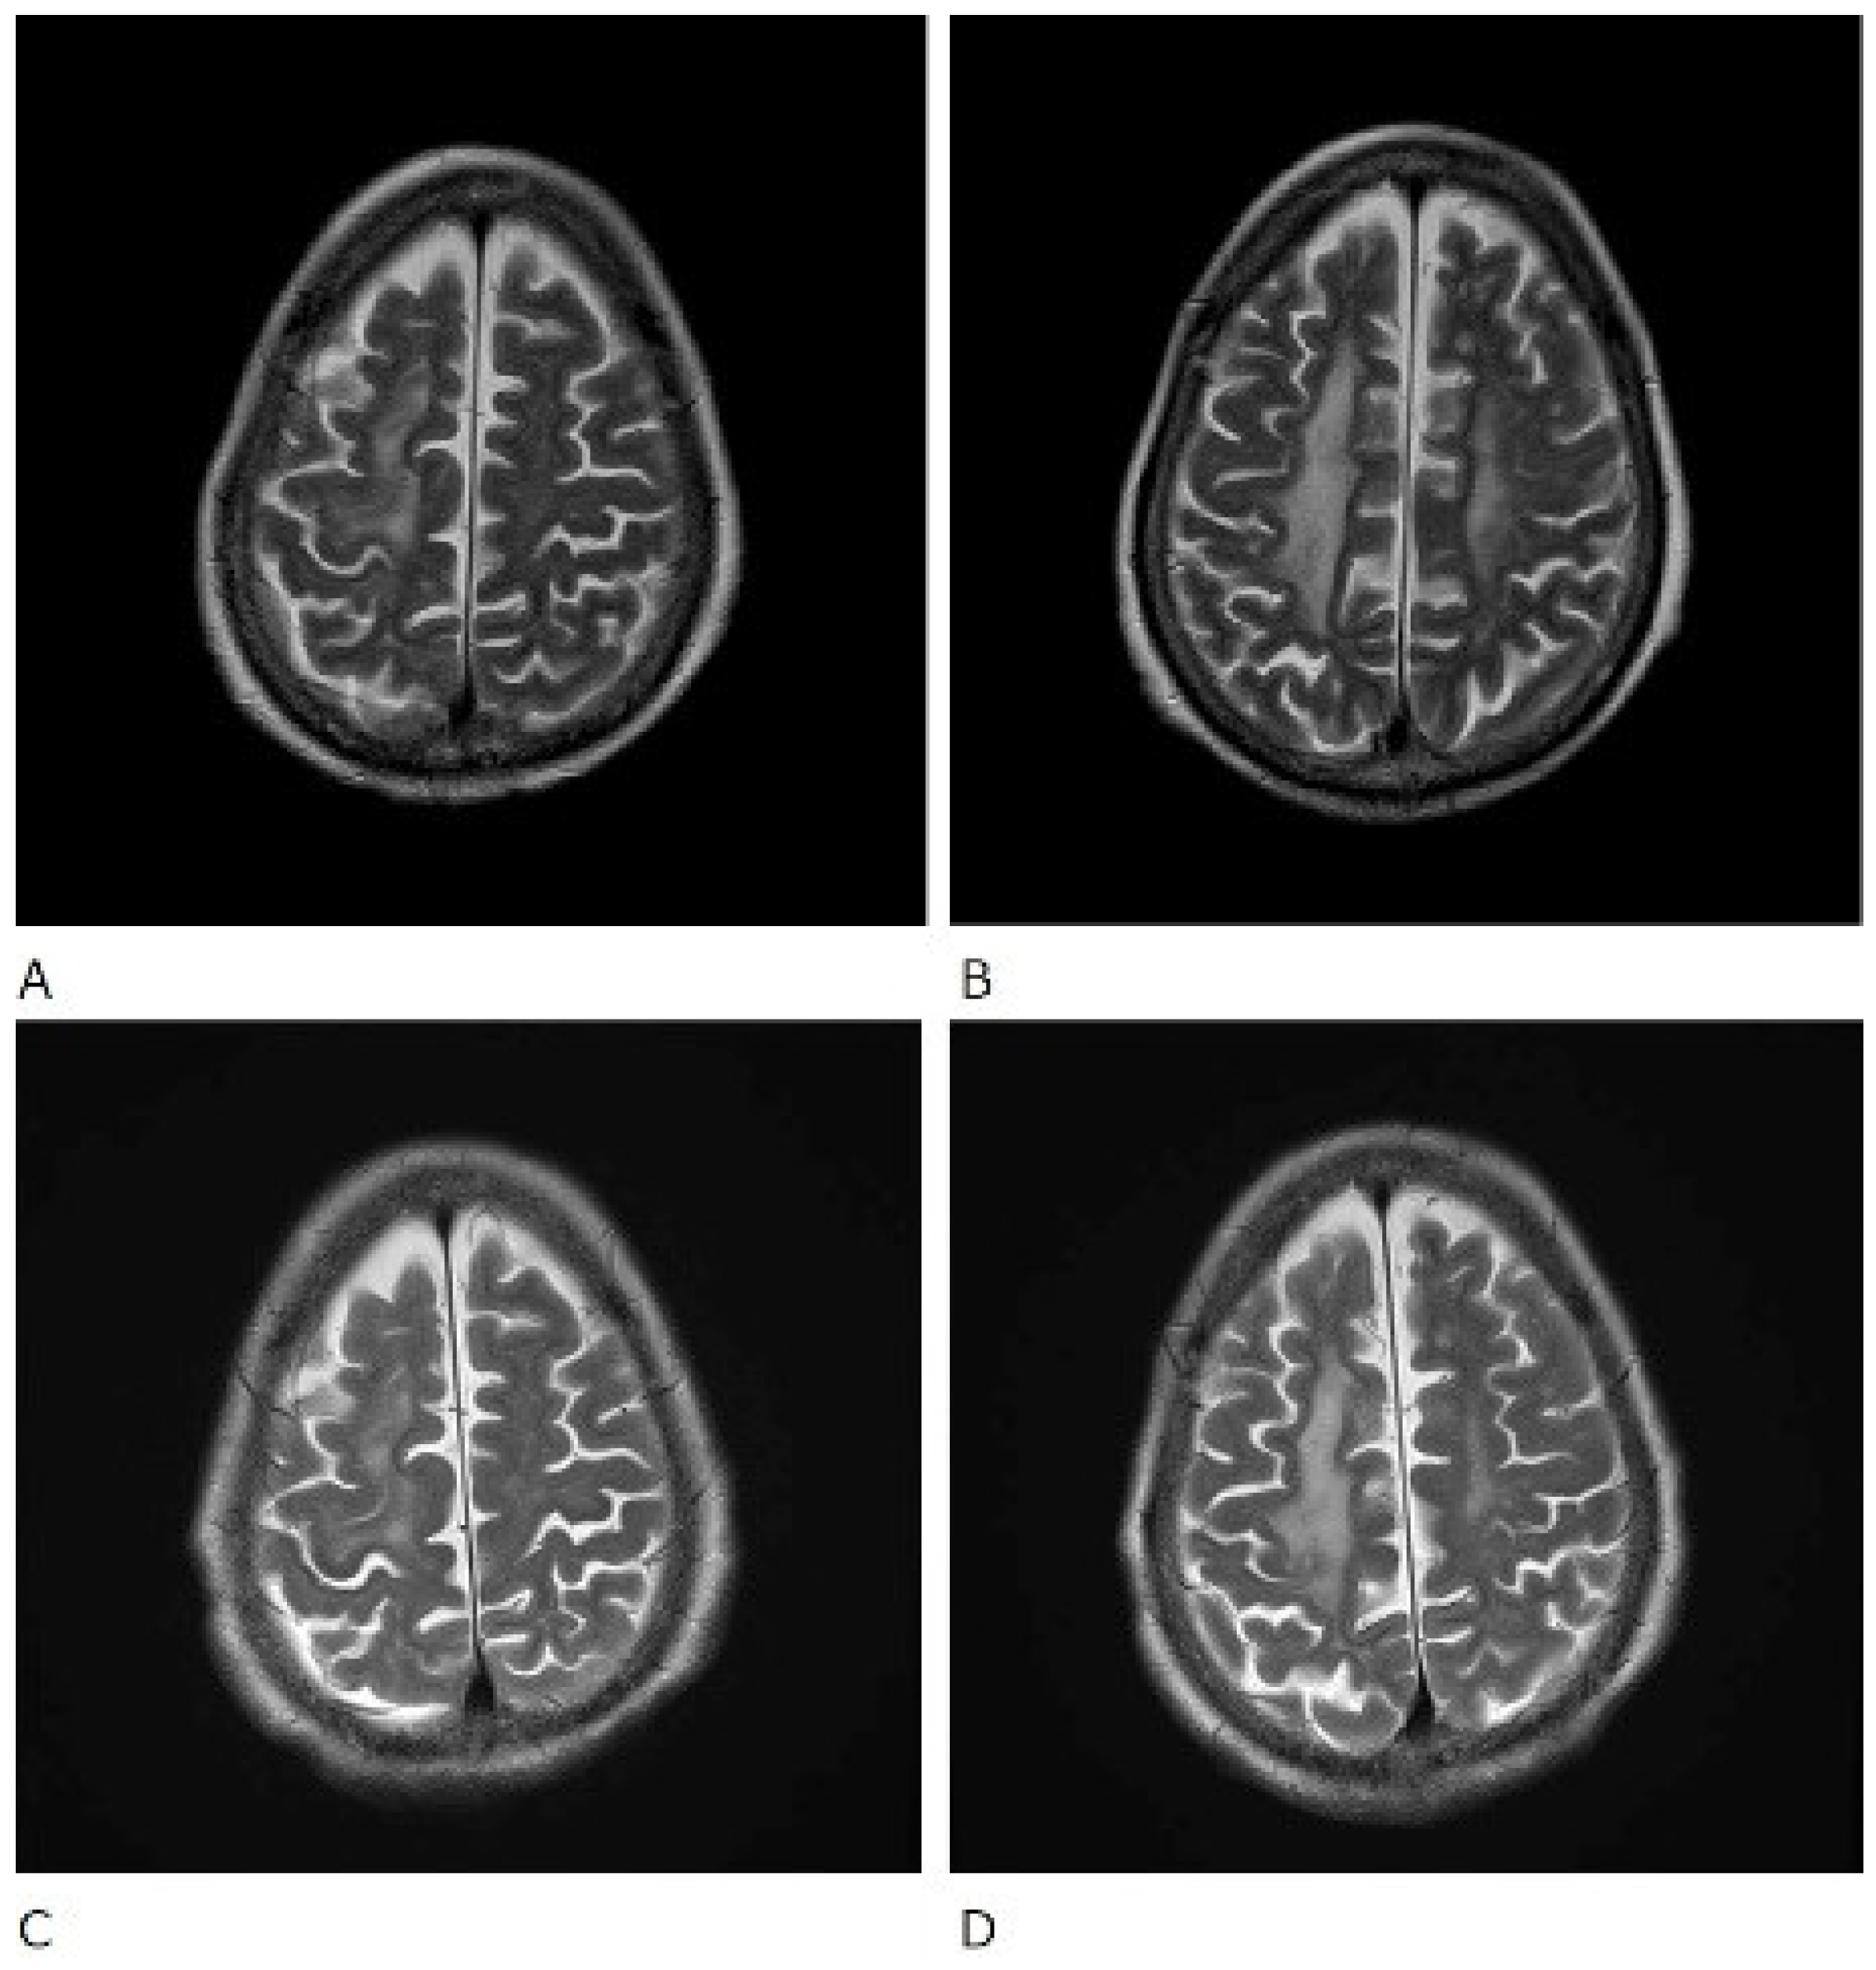

The patient was also tested for infectious diseases but was negative for herpes simplex virus 1, varicella-zoster virus, cytomegalovirus, Epstein–Barr virus, hepatitis B virus, hepatitis C virus, and cryptococcus. Differential diagnosis of non-infectious granulomatous meningitis includes sarcoidosis and tuberculosis. However, there were no other clinical findings, such as bilateral hilar lymphadenopathy, that were indicative of sarcoidosis. Moreover, she had no history of tuberculosis, and a current tuberculosis infection was excluded because no mycobacteria were detected in the CSF; her T-SPOT-TB was negative. Therefore, the patient was diagnosed with rheumatoid meningitis. Prednisolone sodium succinate (40 mg/day; 1 mg/kg/day) was administered by infusion on day 1 to day 9 after admission, and her consciousness level gradually improved. No antibiotics were used. MRI was performed on the 10th day of hospitalisation and showed that the high signal that had been observed in the previous FLAIR sequence had almost disappeared, except in the left frontal region. In contrast, no change was observed in diffuse hyperintensity (T2-WI, FLAIR) of cerebral white matter showing leukoaraiosis (Figure 2 and Figure 3). Since the level of consciousness had improved, her medication was changed to prednisolone 30 mg/day on Day 10 of hospitalisation. On Day 16, her consciousness level recovered to E4V4M6 on the GCS, and she was transferred to another hospital.

Figure 3.

T2-weighted (T2WI) magnetic resonance imaging scans of the brain. Before treatment (A,B) and after treatment (C,D).